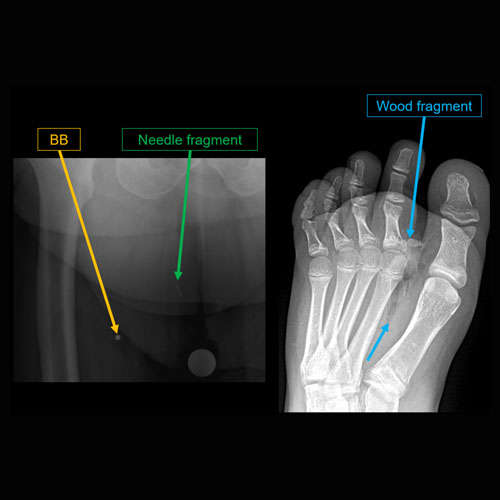

Foot pain after trauma.Exam

There is a foreign body. |

No | NA |

There are fractures. |

Yes | NA |

Soft tissue defect along the medial foot with possible underlying osteomyelitis of the first metatarsal head.

MRI to further evaluate for osteomyelitis.